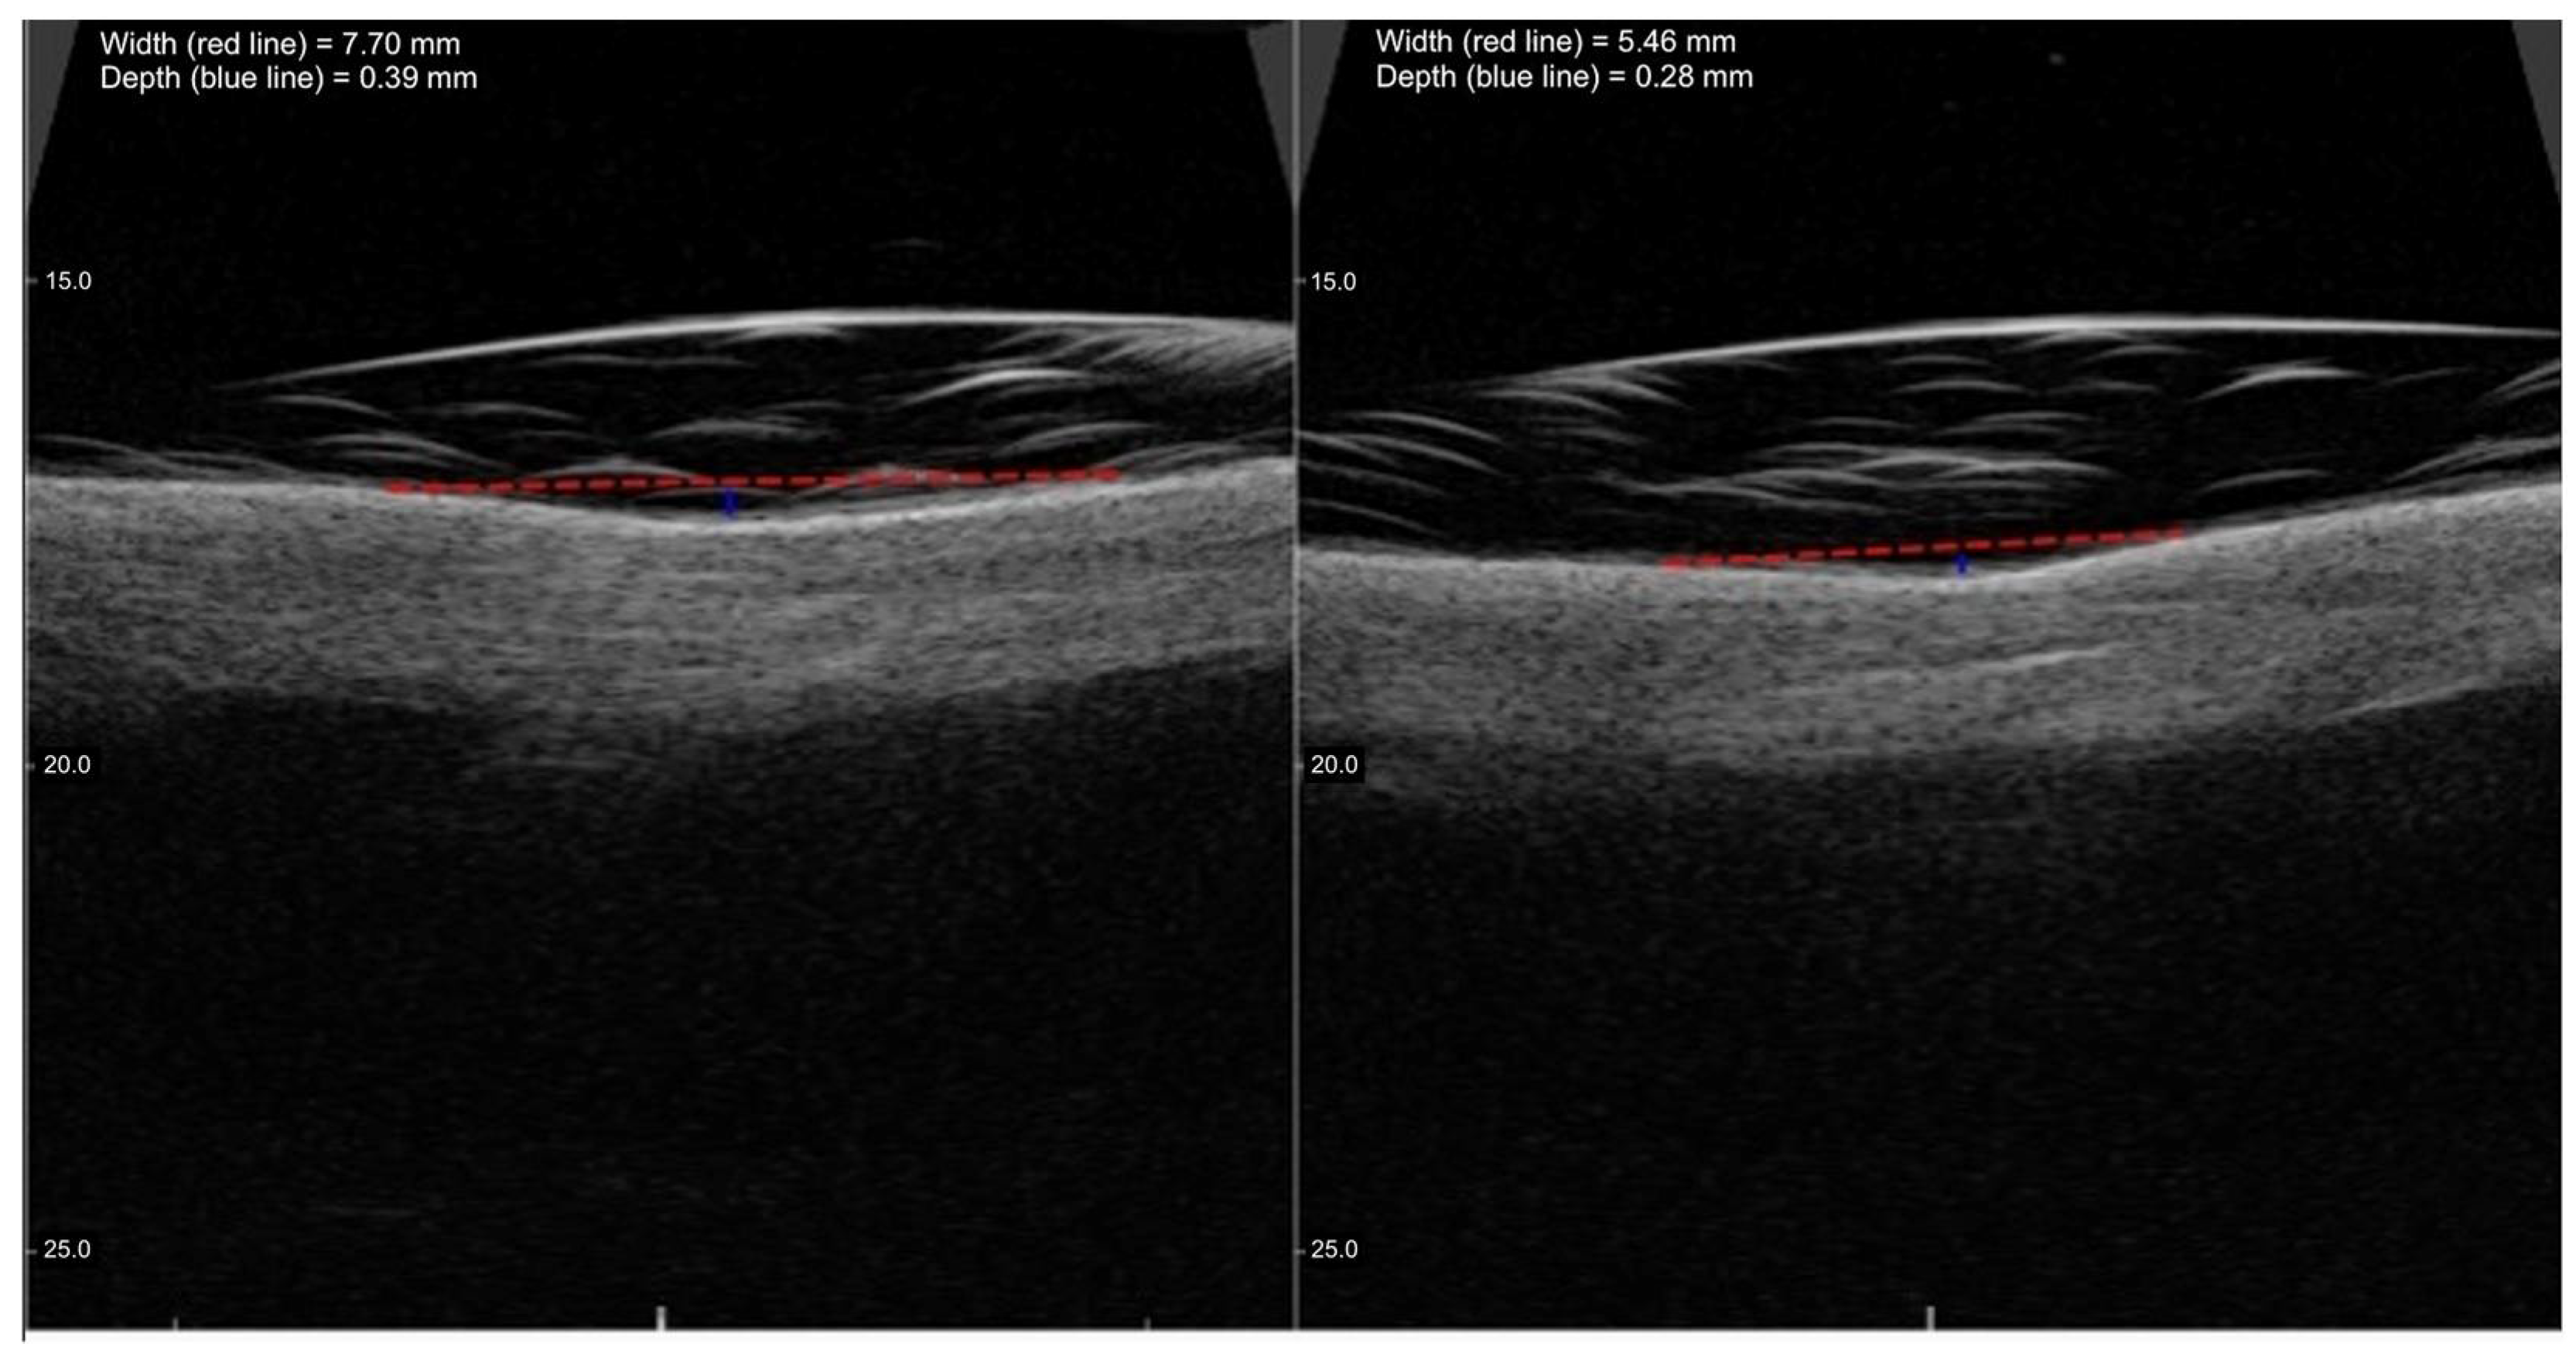

2.3. High-Frequency Ultrasound Evaluation

| Timepoint | Mean Width (mm) | Standard Deviation (Width) | Change vs. Baseline (Width) | p-Value Width | Mean Depth (mm) | Standard Deviation (Depth) | Change vs. Baseline (Depth) | p-Value Depth |

|---|---|---|---|---|---|---|---|---|

| Before Treatments | 6.58 | 2.65 | - | - | 0.34 | 0.16 | - | - |

| Day 14 (14 days after 1st treatment) | 5.88 | 2.47 | −10.64% | <0.001 | 0.31 | 0.15 | −8.82% | <0.01 |

| Day 35 (21 days after 2nd treatment) | 5.20 | 2.33 | −20.97% | <0.001 | 0.27 | 0.13 | −20.59% | <0.001 |

| Day 56–70 (28–35 days after 3rd treatment) | 4.76 | 2.63 | −27.66% | <0.001 | 0.23 | 0.13 | −32.35% | <0.001 |

| Day 118–132 (90 days after end of treatments) | 4.40 | 2.52 | −33.13% | <0.001 | 0.18 | 0.15 | −47.06% | <0.001 |